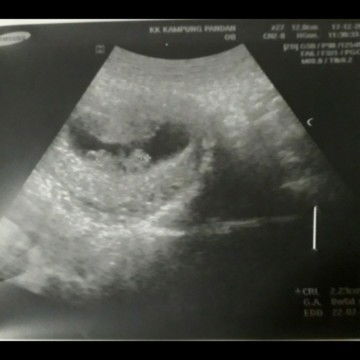

8 weeks or 10 weeks ??

Masa 10 weeks saya baru first time daftar utk buku merah .. saya mmg confident tarikh last period (first day start period is 5 oct 2019) sebab habis nikah and sanding , malam tu saya period , jadi mmg ingat sangat tarikh tu. Baru ni bukak buku merah , doctor scan size baby menunjuk kan baby baru 8 weeks , padahal sepatutnya calculation is 10 weeks .. sampai dokter anggap saya salah date period ? padahal mmg normal flow period (tak penah ada problem ) Does anyone ever had this kind of experiences ?